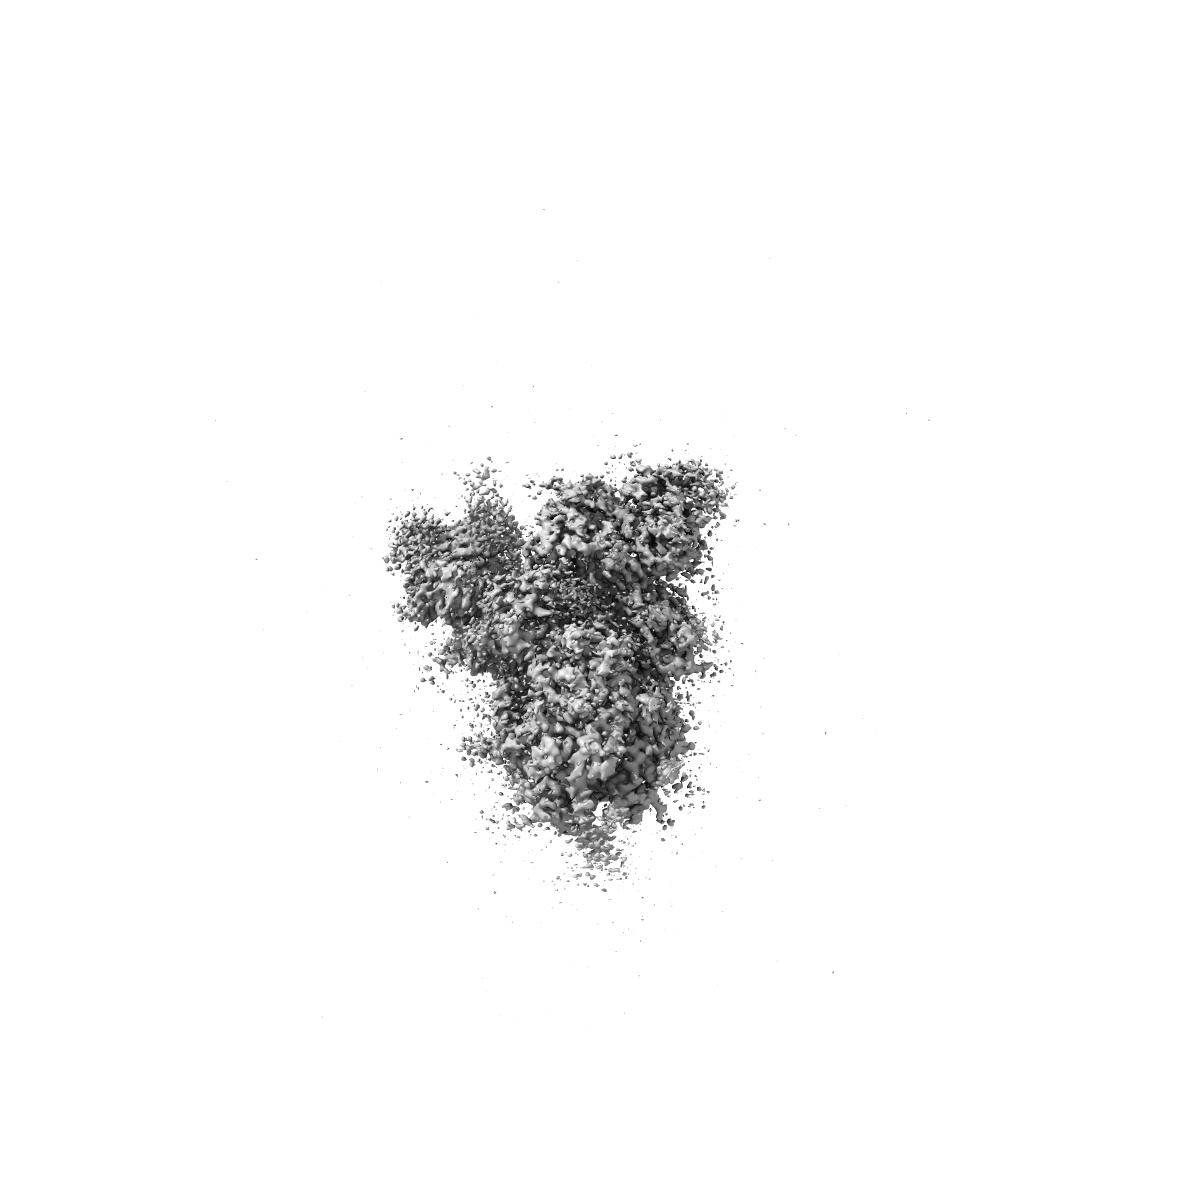

Structure of Covid Spike variant deltaN135 with one erect RBD

Single-particle3.08 Å

Sample: Covid Spike variant deltaN135

Convergence of immune escape strategies highlights plasticity of SARS-CoV-2 spike.

(2023) PLoS Pathog , 19 , e1011308 - e1011308